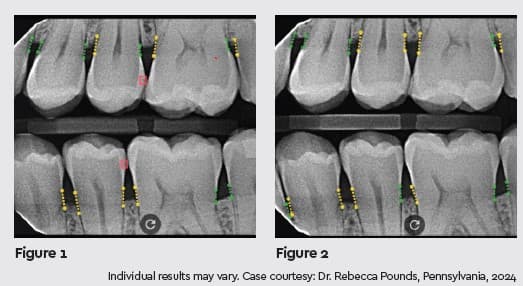

A good example of this process is a recent case in which a 32-year-old male patient was seen at my office for his 6-month recall appointment. At this visit, bitewing x-rays were taken and evaluated, and VideaAI aided in the diagnosis of 2 areas of incipient decay on the distal surfaces of teeth Nos. 13 and 20 (Figure 1). Both areas were treated with CRFP because the decay was still limited to the enamel. When the patient returned for his next 6-month recall visit, a bitewing x-ray showed that the areas had regressed and were not highlighted in VideaAI (Figure 2).